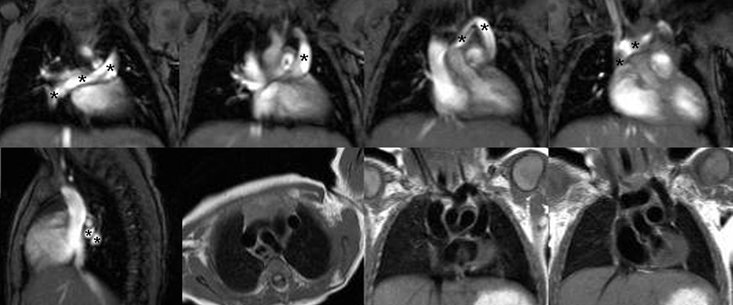

L’atteinte cardiaque peut se faire par propagation de voisinage en cas de tumeurs bronchiques ou médiastinales (A), par voie hématogène en cas de métastases à distance (cf: métastase intra-myocardique d’un cancer ORL illustrée en B), par voie lymphatique ou veineuse prenant les cavités cardiaques droites comme dans les exemples ci-dessous d’extension d’un EOA utérin enclavée dans l’infundibulum (C) ou de tumeur de Grawitz envahissant l’oreillette droite (D).

Envahissement tumoral de la paroi latérale du VG avec hypersignal T2 (séquence STIR) et hypersignal post-gadolinium (PSIR) chez un patient de 49 ans aux antécédents de séminome une quinzaine d’année auparavant avec récidive l’année précédente, traitée par chimiothérapie et extension sous forme de nodules pulmonaires et de métastase cérébrale traitée par radiothérapie. La paroi latérale infiltrée est hypokinétique avec FEVG abaissée à 54%.